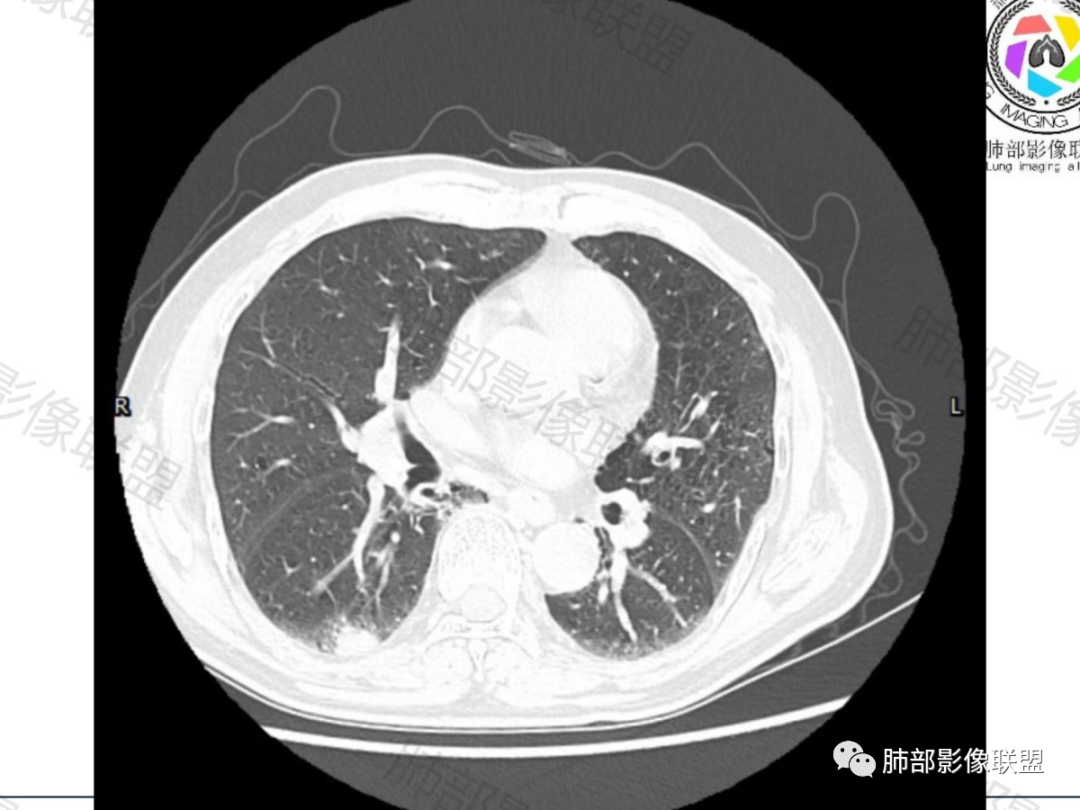

右肺下叶实性结节,肺气肿背景

抗炎治疗后周围渗出减少,结节大小无明显变化

形态呈山丘样改变,边缘膨隆

右肺下叶实性结节,肺气肿背景,山丘,边缘膨隆、指状突起。治疗前边缘有渗出,治疗后结节边界清晰,大小变化不大。胸膜下脂肪间隙不清,增强后轻度不均匀强化,内部沼泽样坏死。

发生于肺边缘的小细胞癌有时会呈半圆形或圆冠状贴服于胸壁下,有老师称之为“山丘征”。经治疗后复查持续存在或增大的山丘影应当想到小细胞肺癌的可能性,尤其是在肺门纵膈淋巴结增大时。

位于胸膜下的周围型Sclc沿着胸膜塑形成长:长轴贴于胸膜面,一侧或双侧与胸膜交为钝角,不侵及相邻肋骨,似山丘状或馒头状(馒头质地软)

位于胸膜下的鳞癌常与胸膜交成锐角

位于胸膜下的腺癌常伴胸膜凹陷征